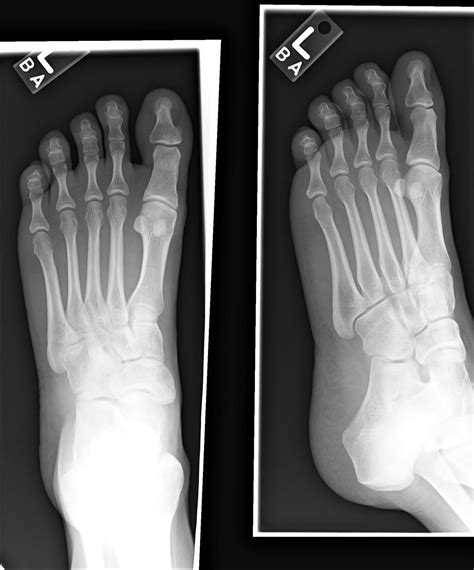

Understanding what constitutes a Normal Foot X Ray is a fundamental aspect of orthopedic diagnostics. When a patient presents with persistent foot pain, swelling, or trauma, a radiograph is often the first imaging modality requested by healthcare professionals. By comparing a patient's imaging against the standard anatomical markers found in a healthy foot, radiologists can effectively rule out fractures, dislocations, or chronic degenerative conditions. This guide delves into the essential components of foot anatomy as seen on X-ray and provides insight into what medical professionals look for during an examination.

The human foot is a complex structure comprised of 26 bones, numerous joints, and soft tissue. A standard radiographic study typically includes three views: the dorsoplantar (top-down), the oblique (angled), and the lateral (side profile). A Normal Foot X Ray will clearly display these bones without evidence of discontinuity or abnormal spacing. Key anatomical regions assessed include:

When a radiologist interprets an X-ray, they follow a systematic checklist to confirm that the images depict healthy anatomy. In a Normal Foot X Ray, the cortical bone edges should be smooth and continuous, indicating no breaks or fractures. Furthermore, joint spaces should be uniform in width, suggesting that there is no loss of cartilage—a common sign of osteoarthritis.

• Alignment: The bones should follow anatomical lines, especially in the midfoot, where the metatarsal bases must align with the cuneiforms.

• Joint Spaces: Clear, visible gaps between bones suggest that cartilage is intact.

• Soft Tissue Shadowing: While X-rays are primarily for bones, a “normal” report will note the absence of deep swelling or foreign bodies in the surrounding soft tissue.